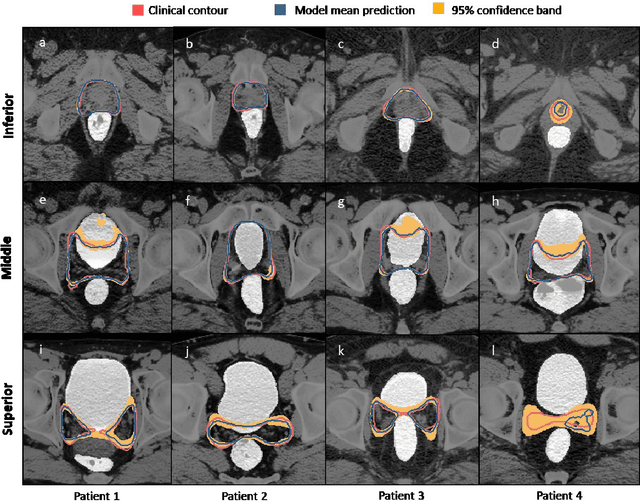

Abstract:In post-operative radiotherapy for prostate cancer, the cancerous prostate gland has been surgically removed, so the clinical target volume (CTV) to be irradiated encompasses the microscopic spread of tumor cells, which cannot be visualized in typical clinical images such as computed tomography or magnetic resonance imaging. In current clinical practice, physicians segment CTVs manually based on their relationship with nearby organs and other clinical information, per clinical guidelines. Automating post-operative prostate CTV segmentation with traditional image segmentation methods has been a major challenge. Here, we propose a deep learning model to overcome this problem by segmenting nearby organs first, then using their relationship with the CTV to assist CTV segmentation. The model proposed is trained using labels clinically approved and used for patient treatment, which are subject to relatively large inter-physician variations due to the absence of a visual ground truth. The model achieves an average Dice similarity coefficient (DSC) of 0.87 on a holdout dataset of 50 patients, much better than established methods, such as atlas-based methods (DSC<0.7). The uncertainties associated with automatically segmented CTV contours are also estimated to help physicians inspect and revise the contours, especially in areas with large inter-physician variations. We also use a 4-point grading system to show that the clinical quality of the automatically segmented CTV contours is equal to that of approved clinical contours manually drawn by physicians.